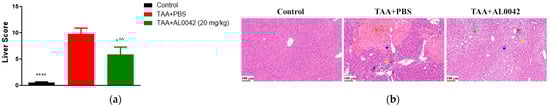

3.5. Activity of AL0042 on Liver Morphology and Inflammation of TAA-Mice